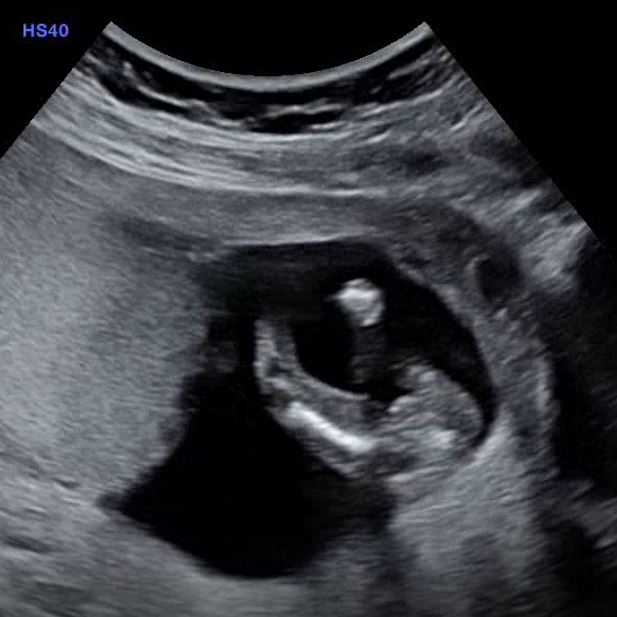

14 weeks pottie shot - girl?

2 days ago we had our private scan for gender. I was 14 weeks 1 day. Tech wasn't sure but she would guess girl.

Attachment 38252